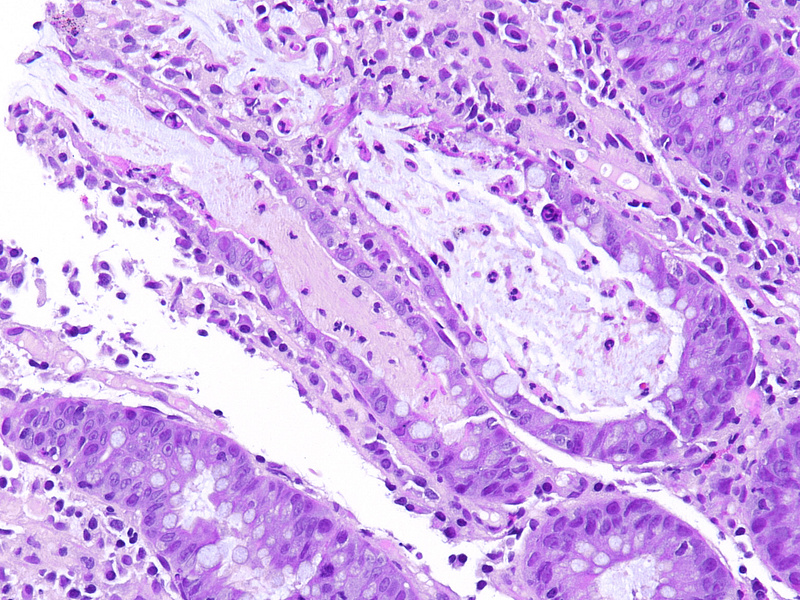

Histology showed mild crypt architecture distortion, increased lamina propria cellularity with mixed inflammatory cell infiltration containing plasma cells, lymphocytes, neutrophils, and scattered eosinophils. Mild basal plasmacytosis was present. The superficial epithelium was flattened and focally eroded (Panels A-B). Crypts showed a prominent loss of goblet cells, with reduced secretion from the remaining ones. Neutrophilic cryptitis with the presence of apoptotic bodies in the epithelial lining was observed. Some crypts were attenuated, lined by flattened epithelium, and contained apoptotic debris and neutrophils. Scattered withering crypts were found (Panels C-D).

These morphological findings of chronic active colitis with increased crypt epithelial apoptosis are suggestive of drug-induced colonic mucosa injury. Considering the patient’s known drug history of Pembrolizumab, Ipilimumab, and Nivolumab treatment, the diagnosis of immune checkpoint-inhibitor (ICI) therapy-associated colitis was made.